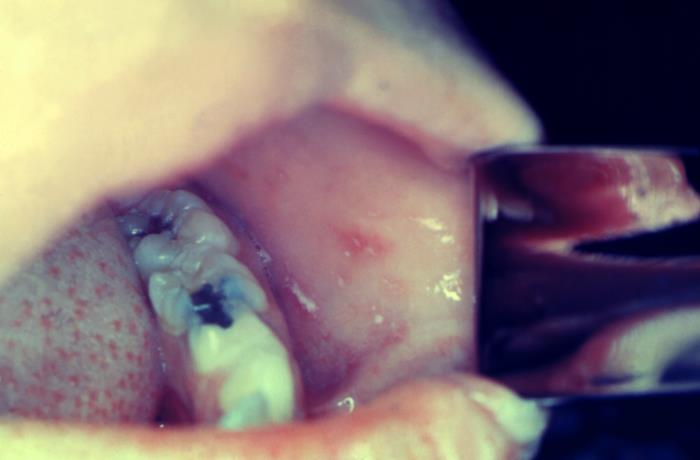

右:口内にできた白いできもの(コプリック斑)。はしか特有の症状の1つ。

初期症状は風邪に似ていますが、いったん解熱後に約40度の高熱、全身の発疹、口の中の白いできもの、結膜炎などが引き起こされます。